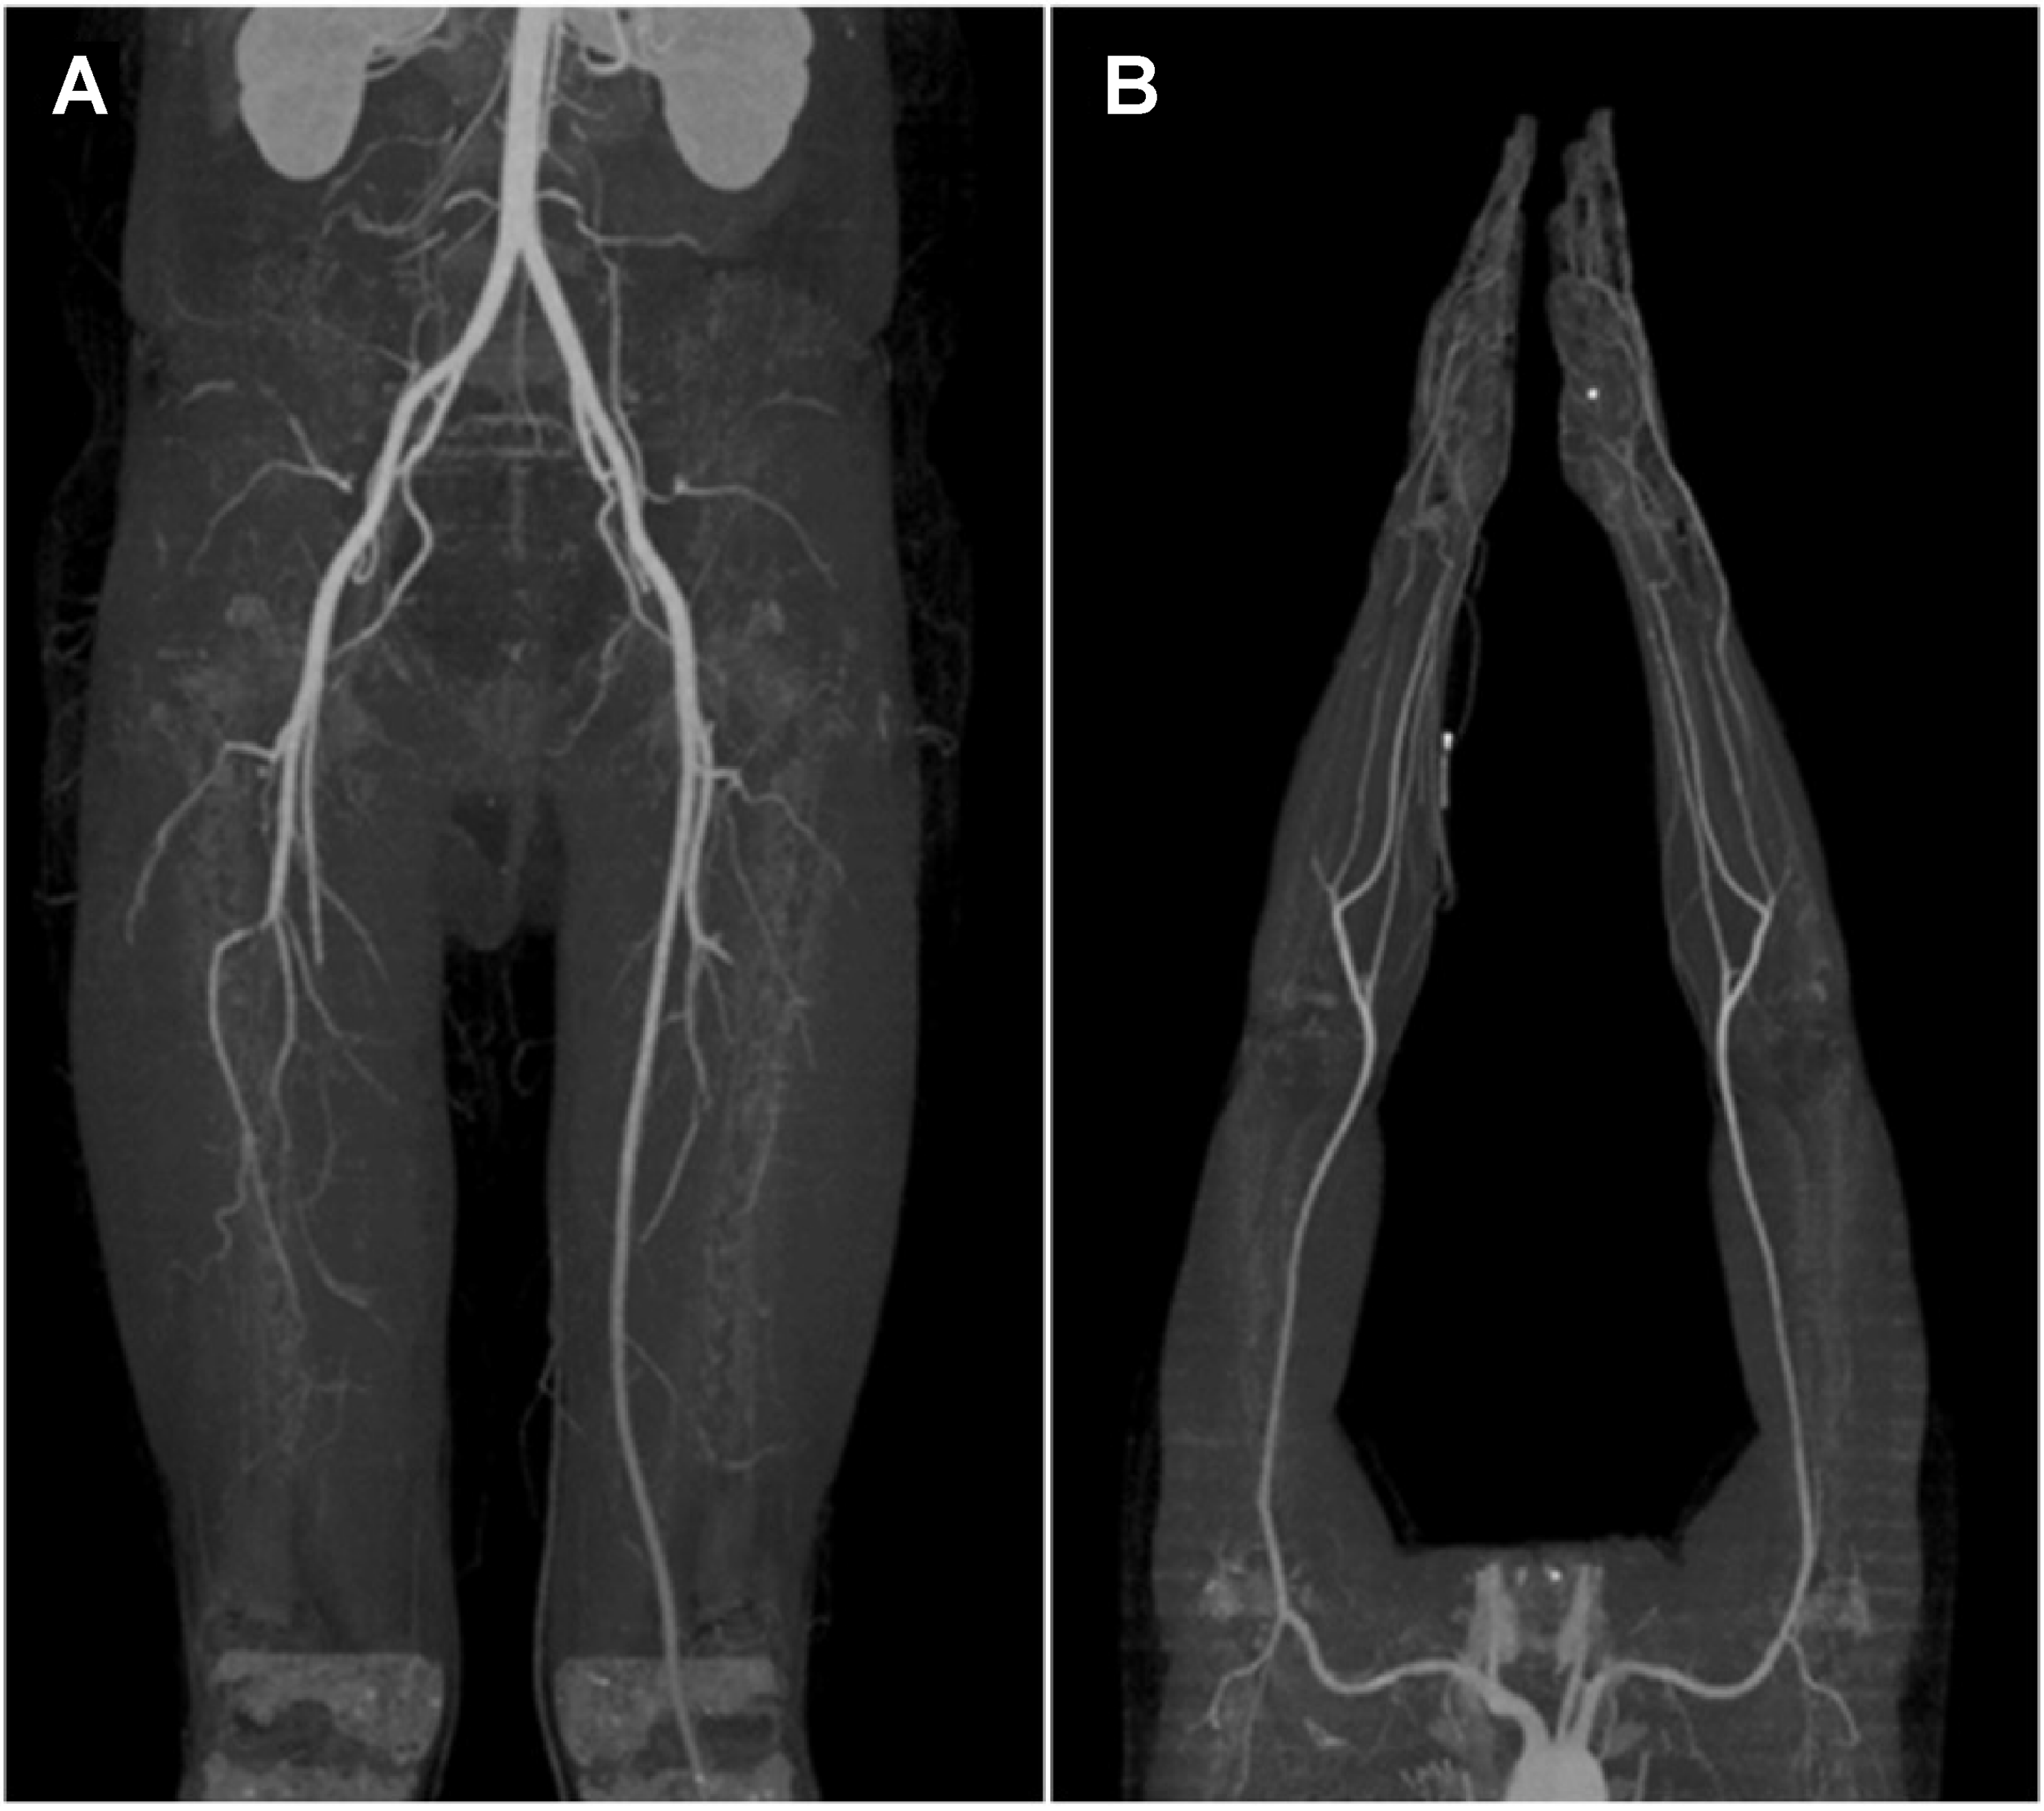

Upon physical examination, the dorsalis pedis artery was hardly palpable, and poor blood flow was confirmed through handheld Doppler examination. Based on these findings, and considering that the patient was a young man with a smoking history of >20 packs per year, thromboangiitis obliterans, known as Buerger’s disease, was suspected. Upper- and lower-extremity computed tomography angiography was performed for confirmation; the related findings showed abrupt occlusion of the right popliteal artery (Figure 2A) and both ulnar arteries with corkscrew collaterals (Figure 2B). The patient was diagnosed with Buerger’s disease, and percutaneous transluminal angioplasty (PTA) was performed after consultation with a cardiologist.

Figure 2.

(A) Lower extremity computed tomography angiography showing abrupt occlusion of the right popliteal artery; (B) Upper extremity computed tomography angiography showing total occlusion at both distal ulnar arteries with corkscrew collaterals.